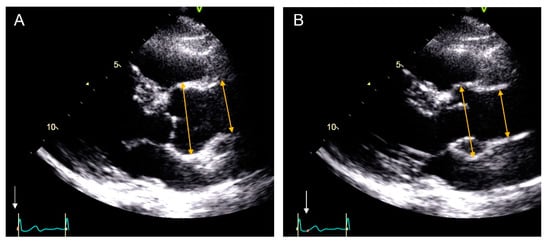

2.1. Echocardiography